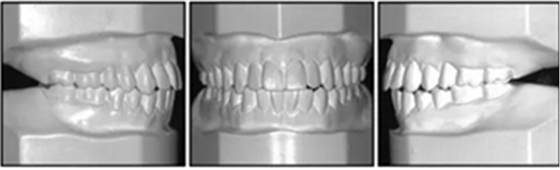

口內(nèi)相及模型:雙側磨牙、尖牙I類關系,良好的牙尖交錯關系,覆合、覆蓋正常。

治療后50個月:治療結果基本保持穩(wěn)定,左側可見輕微復發(fā)跡象,這可能與患者的TMJ狀況有關,需要進一步治療。